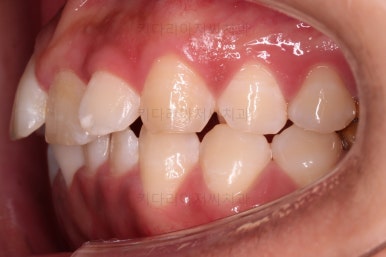

초진 시, 입 안의 모습이에요.

위아랫니가 삐뚤고 교합이 약간 맞지 않네요.

입 안만 보면 심플하게 교정하면 되겠다 싶지만, 문제는 다른 곳에 있었어요.